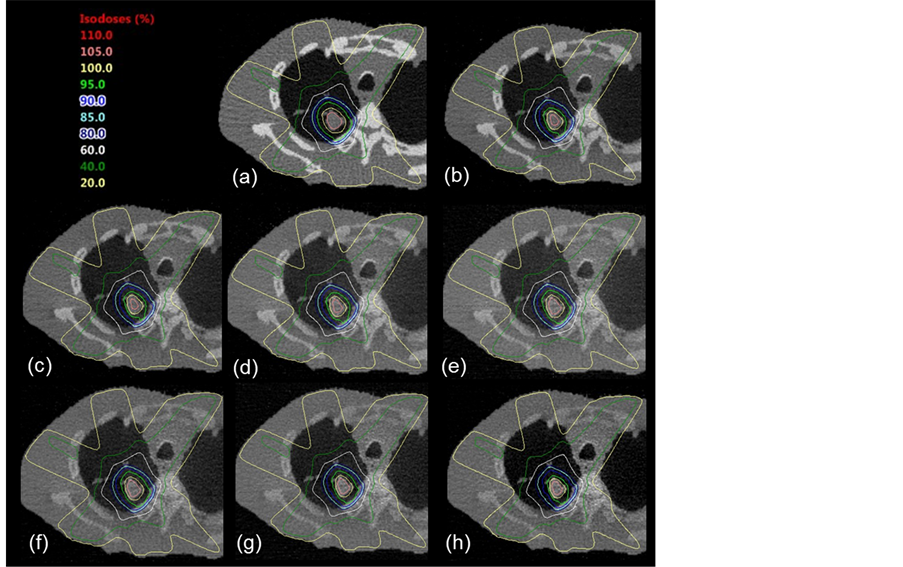

Figure 6 shows the dose distribution in the lung image calculated from the MDCT image. Figure 7 shows the dose distribution in the CBCT image for each ED curve without cupping artifact correction, and Figure 8 shows the dose distributions with cupping artifact correction. Subfigure 7, 8A shows conventional five-field planning, and subfigure 7, 8B shows 1-arc VMAT planning. The dose distribution in the primary photon image (a) is similar to that in the MSCT image (Figure 6(A)); on the other hand, the images (b)-(h) of the dose distributions for different scattered photon ratios without cupping artifact correction were different from those of the MSCT plan in terms of the shape of the isodose curves near the tumor. In the conventional planning (Figure 8(A)) and the VMAT planning (Figure 8(B)), these dose distributions were similar to those of the MSCT planning regardless of the amount of scattered photons.

Figure 7. Dose distributions using the CBCT image without cupping artifact correction. These lung images were reconstructed by using scattered photons at different ratios; (a): only primary photons, (b): 5%, (c): 10%, (d): 20%, (e): 40%, (f): 60%, (g): 80%, (h): 100% with scattered photons. (A): conventional five-field planning, (B): 1-arc VMAT planning.

Figure 8. Dose distributions using the CBCT image with cupping artifact correction. (a): only primary photons, (b): 5%, (c): 10%, (d): 20%, (e): 40%, (f): 60%, (g): 80%, (h): 100% with scattered photons. (A): conventional five-field planning, (B): 1-arc VMAT planning.

Figure 9. Results of the γ analysis, (A) shows conventional five-field planning and (B) shows the 1-arc VMAT planning. The criteria for the pass rate were a 3% absolute dose and a 3-mm distance agreement.

the dose distribution in the MSCT planning. The pass rate of the primary photon image was near 100%; on the other hand, the pass rates of the images with scattered photons were significantly smaller than the pass rate of the primary photon image. Moreover, the pass rates of the images with cupping artifact correction were improved and did not depend on the amount of scattered photons.

For the calculated dose distribution results in the lung image, the dose distribution in the primary photon image (Figure 7, Figure 8(a)) was similar to that in the MSCT image (Figure 6) with conventional and VMAT planning. On the other hand, the dose distributions using scattered photon images (Figures 7(b)-(h)) differed from those in the MSCT planning in terms of the shape of the isodose curves near the tumor. Therefore, the γ pass rates of the conventional and VMAT dose distributions in the scattered photon images were reduced, respectively, by 7.5, 3.6% (scatter, 5%), 22.7, 10.5% (scatter, 10%), 30.5, 11.9% (scatter, 20%), 33.8, 21.3% (scatter, 40%), 25.3, 16.7% (scatter, 60%), 19.4, 11.3% (scatter, 80%), and 13.8 13.5% (scatter, 100%) relative to those in the MSCT planning (Figure 6(A)). Moreover, the γ pass rate of the dose distribution with scattered photons at a ratio of 40% was most decreased because of the degraded image uniformity. On the other hand, in the results of the dose distribution with cupping artifact correction shown in Figure 8, dose distributions near the tumor were similar to those in the MSCT planning, and these dose distributions did not depend on the amount of scattered photons. Therefore, results of the γ pass rates with cupping artifact correction in the conventional and VMAT planning were significantly improved, respectively, by 0.5, 2.3% (scatter, 5%), 1.6, 2.6% (scatter, 10%), 1.3, 2.4% (scatter, 20%), −0.6, 2.0% (scatter, 40%), −0.7, 2.1% (scatter, 60%), −0.5, 2.4% (scatter, 80%), and 0.4, 3.2% (scatter, 100%) relative to those in the MSCT planning. In these results, the cupping artifact correction method was more favorable to the VMAT plan, because, the area of dose deviations caused by the cupping artifact was increased in the VMAT plan than these of the conventional plan (the VMAT plan irradiated large area of the patient body than the irradiated of conventional plan).